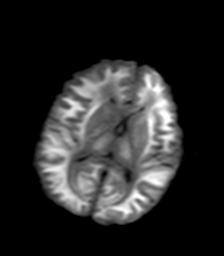

发热、头痛伴精神异常1周

较对称性脑白质异常信号,深部白质t2明显低信号(铁质沉积过多?)

考虑脑白质病变,请结合临床病史及实验室检查进一步分析。

f 23岁